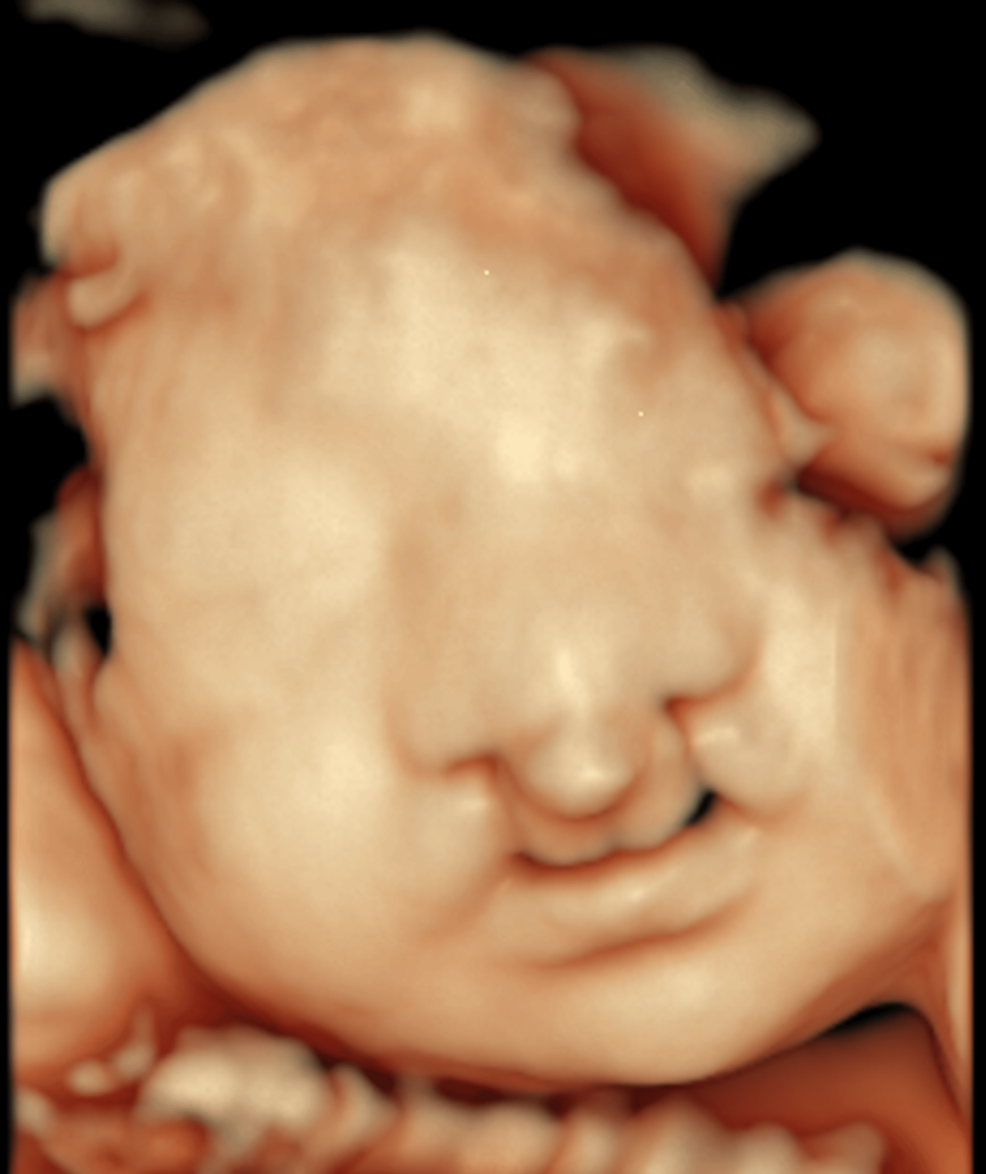

Things That Could Have Been Brought To My Attention Yesterday! Gallery Things That Could Have Been Brought To My Attention Yesterday! By Nicole Angemi|2025-02-23T10:59:55-05:00February 23rd, 2025|Pregnancy, Congenital Anomaly, Women's Health, The Gross Room, MEDICAL| Read More 18